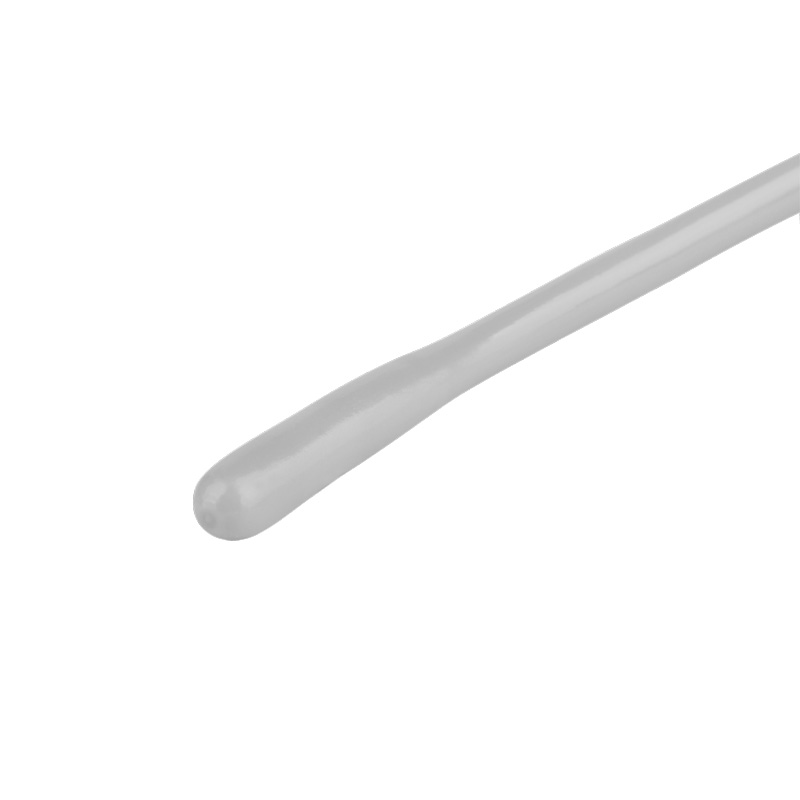

Tempertuursonde voor Lifevet

Temperatuursonde voor Lifevet 8M / 8C / 12M

Kan zowel oesophagaal als rectaal gebruikt worden